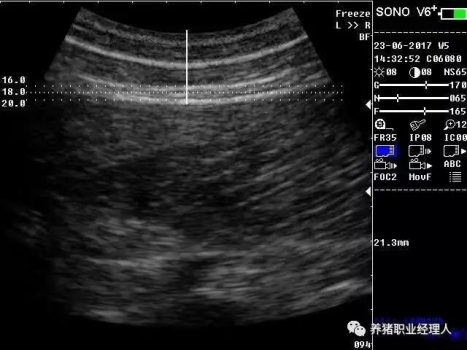

根據(jù)以上表格,活體測(cè)膘與實(shí)體測(cè)膘的相關(guān)分析及活體膘厚與胴體瘦肉率的相關(guān)分析結(jié)果證明,最后肋骨處和腰薦結(jié)合處離背中線(xiàn)5cm處(B5、C5)可作為活體測(cè)膘的最佳部位。 根據(jù)中華人民共和國(guó)農(nóng)業(yè)行業(yè)標(biāo)準(zhǔn)(NY/822-2004)種豬生產(chǎn)性能測(cè)定規(guī)程規(guī)定:生產(chǎn)性能背膘值運(yùn)用A超儀器測(cè)量的需測(cè)定腰薦椎結(jié)合處(P1)、胸腰椎結(jié)合處(P2)距背中線(xiàn)左側(cè)5cm處,兩點(diǎn)背膘厚平均值。生產(chǎn)性能背膘值運(yùn)用B超儀器測(cè)量的需測(cè)定倒數(shù)第三和第四肋骨間距背中線(xiàn)左側(cè)5cm處背膘厚。 2.3 剔剪剪毛 因?yàn)槌暡ㄊ遣荒茉诳諝庵袀鞑サ?,所以在利用儀器測(cè)量之前,先用剔剪剪去測(cè)定部位的豬毛,方便測(cè)量?jī)x器探頭與豬皮膚的無(wú)縫接觸。剪毛面積一般為5cm×5cm左右。此時(shí)若皮膚死皮結(jié)痂較多,便可用溫水擦洗去痂。 2.4涂耦合劑 耦合劑是檢測(cè)儀探頭與豬皮膚之間的中間潤(rùn)滑劑,作為超聲波從儀器發(fā)出到豬體表和從豬體表回到儀器的傳播介質(zhì)。所以耦合劑的作用是排除探頭與豬體表之間的空氣和作為超聲波傳播的介質(zhì)。它是準(zhǔn)確測(cè)定背膘所不能缺少的。 2.5 正確測(cè)量 因?yàn)樨i體表脂肪分為三層。所以不管是用A超還是B超,我們一般都能同時(shí)測(cè)量到三個(gè)數(shù)值,而正確反映豬只體況的是第三個(gè)數(shù)值。如圖所示:

測(cè)量時(shí),盡量讓豬只安靜,避免豬只弓背或塌腰而使測(cè)量數(shù)據(jù)出現(xiàn)偏差。探頭應(yīng)直線(xiàn)平面與豬背正中線(xiàn)縱軸面垂直,不可斜切。同時(shí)探頭應(yīng)與豬背密接且不重壓。 2.6 讀取記錄數(shù)據(jù) 若為A超,讀取儀器亮三個(gè)指示燈時(shí)的數(shù)值,記錄下來(lái)。若為B超,觀察并調(diào)節(jié)屏幕影響,獲得理想影像時(shí)即凍結(jié)影像,測(cè)量背膘厚和眼肌面積,并加以說(shuō)明標(biāo)記。影響打印或保存處理。 3、通過(guò)背膘測(cè)定指導(dǎo)豬生產(chǎn)飼喂管理 以妊娠母豬為例: 表3 妊娠母豬適宜背膘值范圍